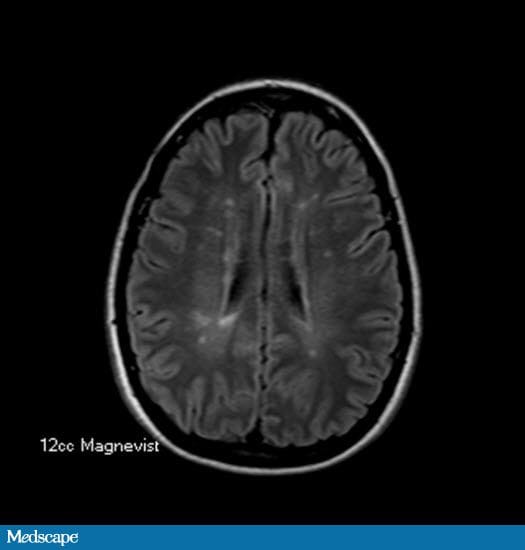

From www.medscape.com